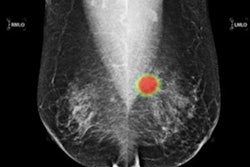

AI software developer Lunit has signed a three-year agreement to supply Capio Saint Göran Hospital in Stockholm, Sweden, with its Insight MMG software to serve as an independent reader of screening mammography exams.

Instead of the traditional approach of double reading by radiologists, the large private hospital in Sweden will use the AI software as a second reader along with a radiologist as first reader. Capio Saint Göran Hospital anticipates that with the integration of this software, its radiology department will be able to interpret 78,000 screening mammography exams each year, according to Lunit.